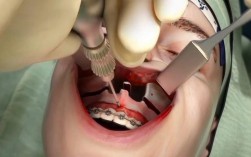

针对骨量不足靠近上颌窦的情况,种植牙医生通常不会直接种植,而是会采用以下上颌窦提升术来增加骨量,确保种植体安全植入:

- 手术过程: 在缺牙位置的牙槽嵴顶做一个小切口,翻开牙龈骨膜瓣,暴露上颌窦前外侧壁,在窦底开一个“窗”,小心地将上颌窦粘膜完整剥离并向上推起,将骨移植材料(自体骨、异体骨、人工骨或混合物)填入剥离出的空间,将骨膜瓣复位缝合。

内提升术(闭合式/经牙槽嵴顶):

- 适用情况: 剩余骨高度中等(通常5-10mm),骨质量尚可。

- 手术过程: 不需要切开上颌窦外壁,在缺牙位置的牙槽嵴顶做一个小切口,用特制的骨凿或超声骨刀,在窦底骨板上小心地敲击或抬起,将上颌窦粘膜整体向上推起,将骨移植材料填入抬升的空间,缝合伤口。